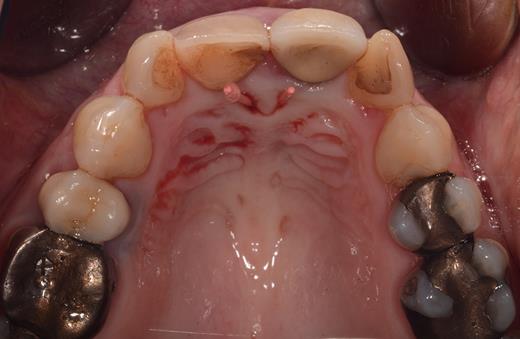

Clinical examination revealed two small mucosal openings on either side of the incisive papilla, which could be probed partially (Fig. 1). Palpation of this area was painful. Two gutta-percha points were inserted into the two openings (Fig. 2). The cone beam computed tomography (CT) confirmed two patent NDPs with oronasal communication (Fig. 3).

Occlusal view of the maxillary arch presenting two small openings of the mucosa with two inserted gutta-percha points on either side of the incisive papilla.